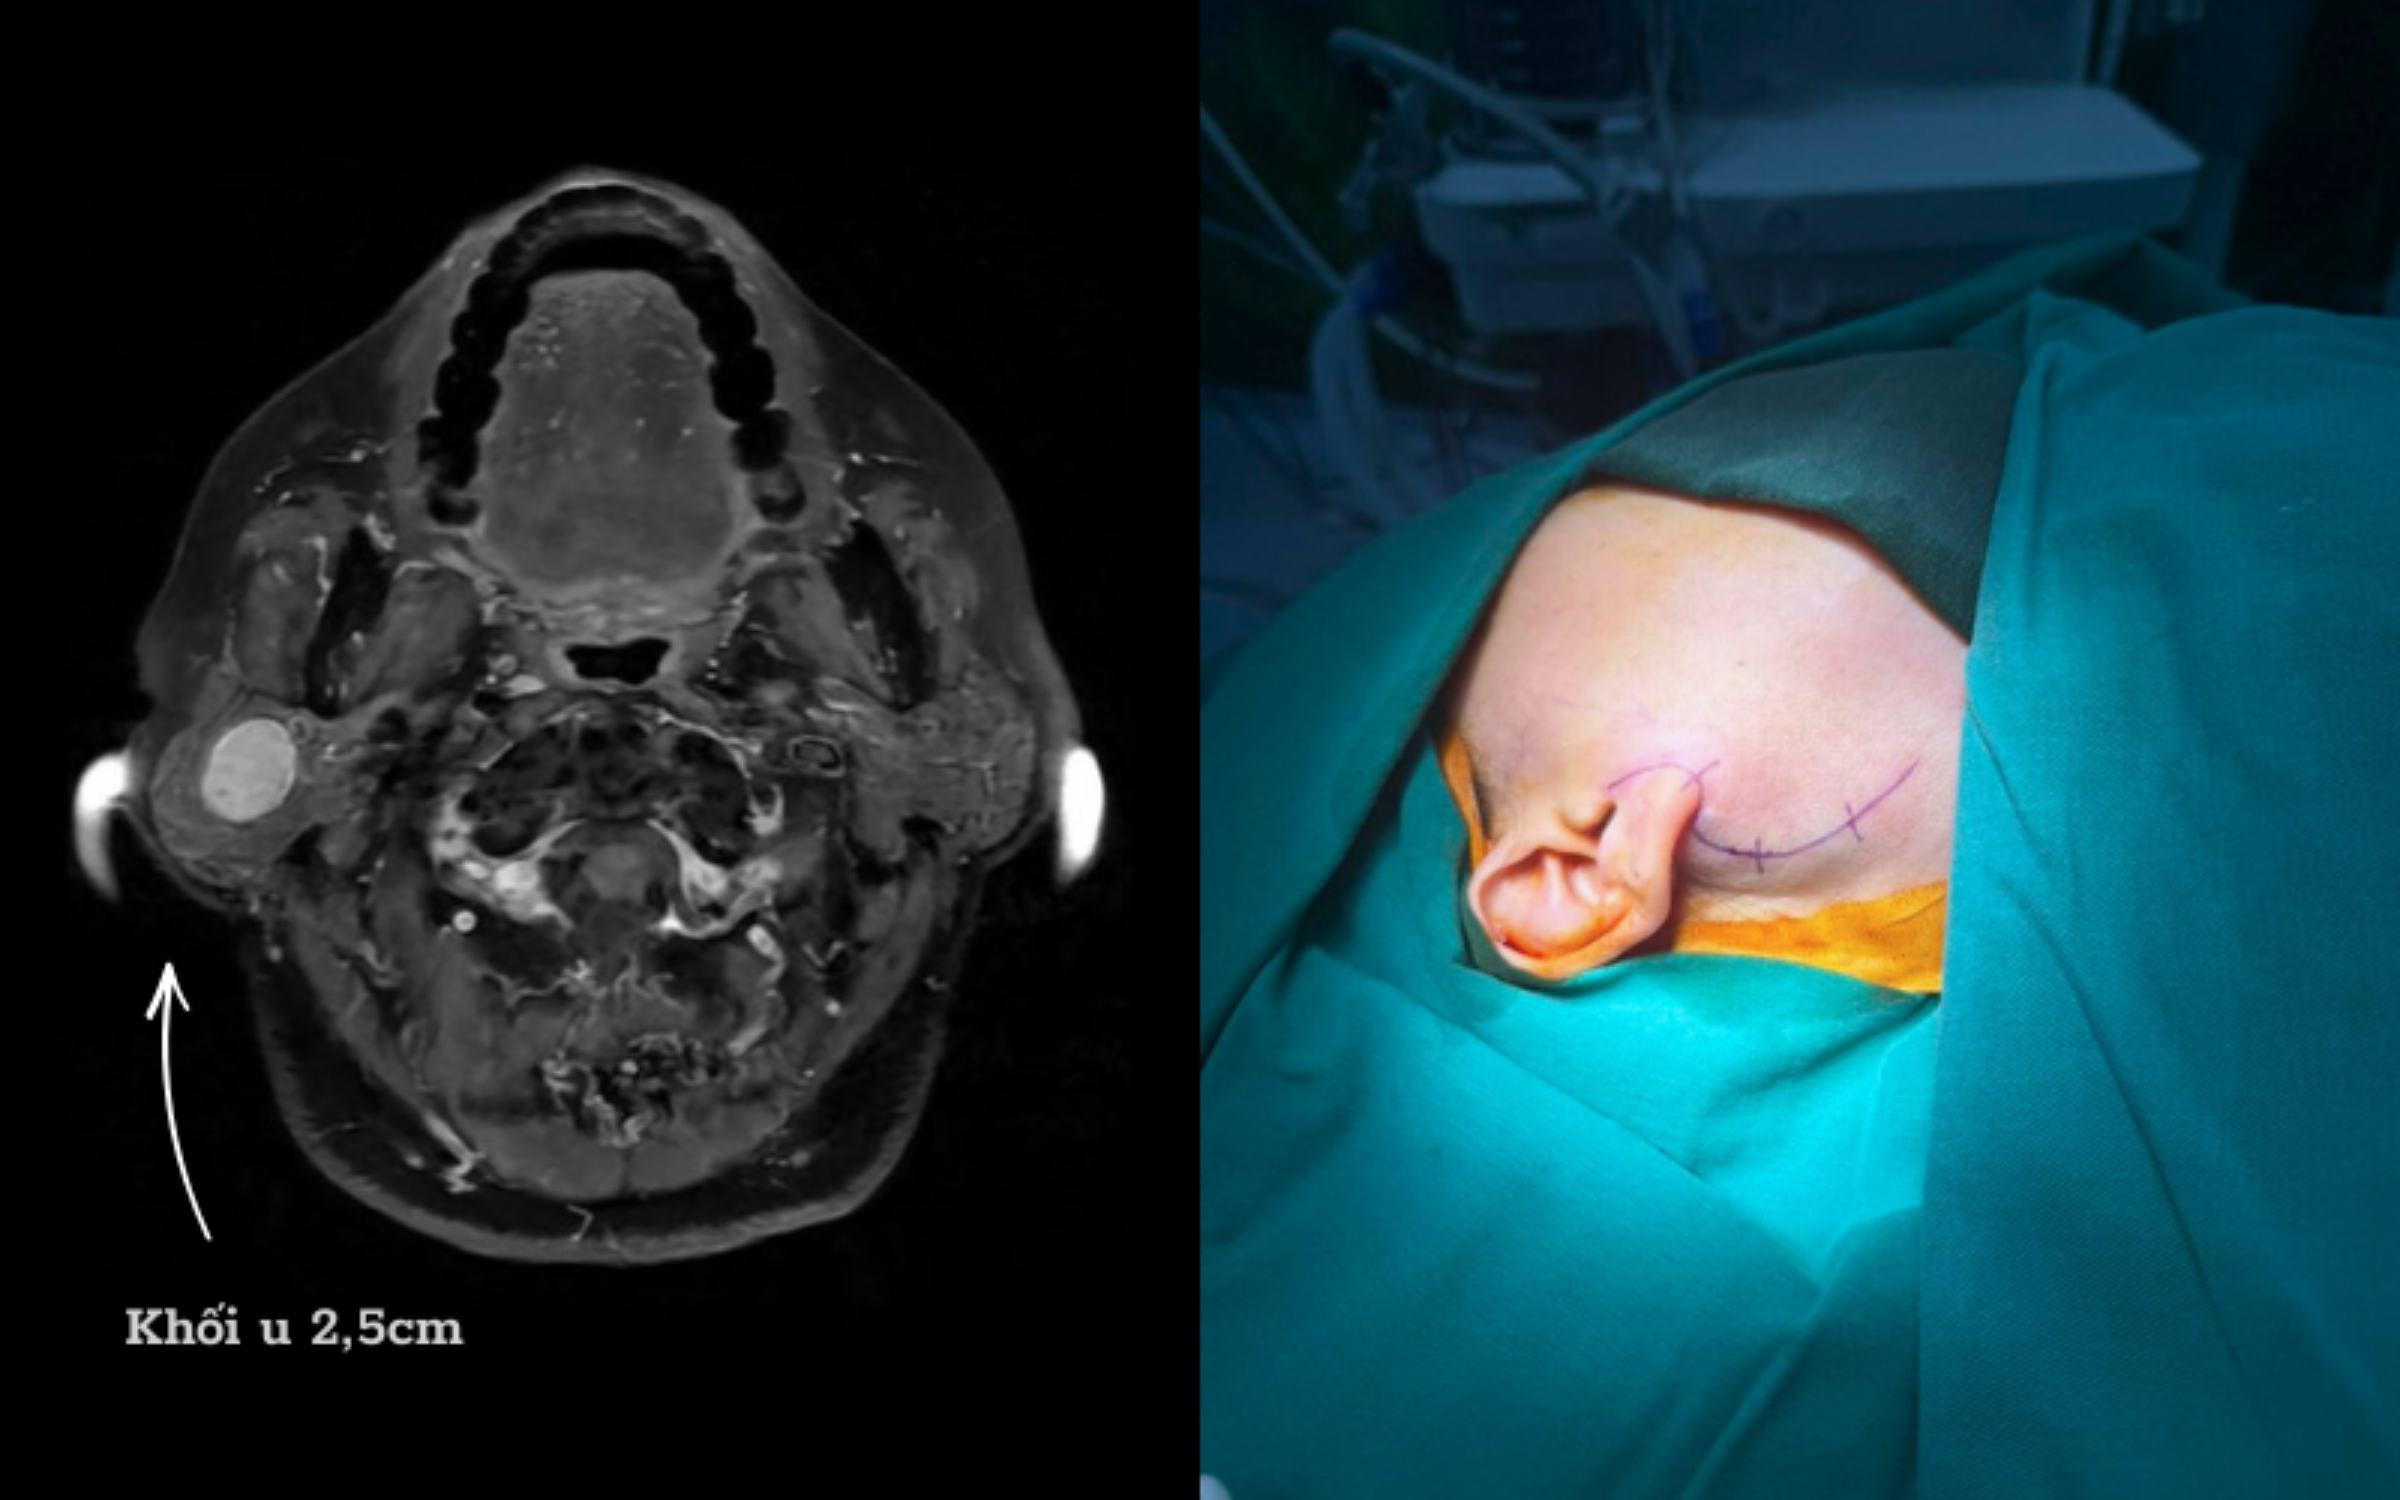

The patient's parotid gland tumor was in a complex position. Photo: Hong Ngoc General Hospital |

The patient's parotid gland tumor was in a complex position. Photo: Hong Ngoc General Hospital

The hospital has applied NIM in hundreds of cases, notably a female patient, 73 years old, who had a right parotid gland tumor for many years, presenting with swelling at the jaw angle and discomfort. Although early surgery was indicated, the patient delayed due to fear of facial paralysis, causing the tumor to grow larger, compress the nerve, and complicate the surgery. Faced with this situation, Doctor Quang and his team used a new generation nerve monitor (NIM) to safely dissect the tumor.

Patient D.'s surgery lasted 3 hours. The tumor was completely removed without requiring total parotidectomy. Post-surgery, the patient recovered quickly, experienced no facial nerve paralysis, and maintained facial symmetry and aesthetics.